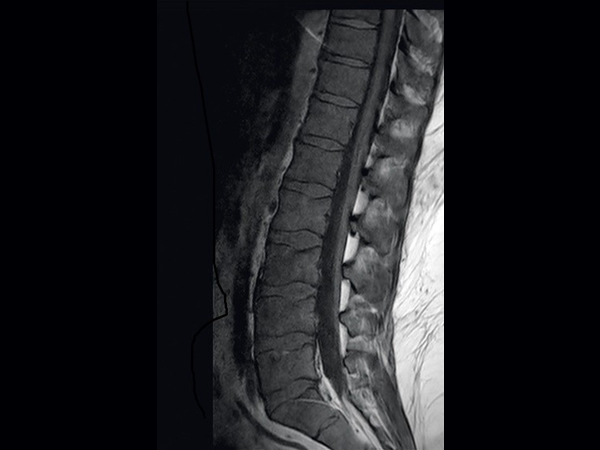

This is a lumbar spine examination of a young obese patient (170 kg) with right sciatic pain. The main difference in the protocol for this obese patient is that the voxel size is around 15-20% larger than in our standard protocol. This patient's weight will vastly increase the minimum TR requirements under the SAR modelling of any 3T scanner. The larger voxel helps both in reducing this increase in scan time and reduces SAR.The MultiTransmit technology evens out the flip angle and SAR across these large fields of view, even when filled with such a large patient, and the dStream coils and SmartSelect technology allows maximum penetration to allow for excellent SNR.The images demonstrate the high SNR provided by dStream and achieved with SmartSelect, which uses a quantitative method to determine and activate all coils that increase SNR. Imaging penetrated 150 mm of fat to reach this patient’s lower L-spine.

Sagittal T2w SPAIR